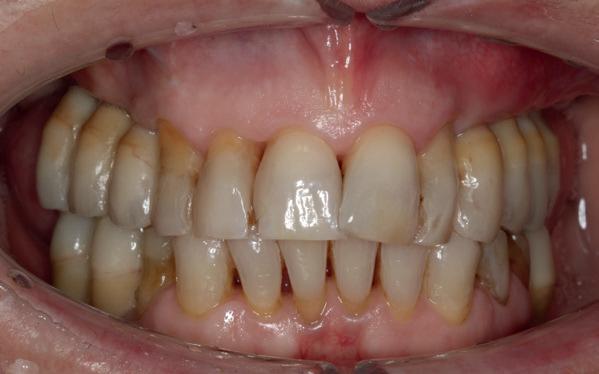

Mevrouw werd naar het Dental Design Center verwezen om een complex probleem aan het bovenfront te beoordelen en indien mogelijk te behandelen. Tien jaar geleden zijn er om esthetische redenen op de 12, 11, 21 en 22 kronen geplaatst. Helaas bleek achteraf een wortelkanaalbehandeling van de 22 noodzakelijk. Na een aantal jaar ontstond er weer een infectie apicaal aan de 22 en werd er een apex uitgevoerd. Helaas had deze behandeling niet het beoogde resultaat. Twee weken voordat ze bij mij op consult kwam, is het element geëxtraheerd en is er een partiële plaat geplaatst als tijdelijke oplossing (foto 1-3).

Na de IPP (esthetisch/functionele) analyse blijkt dat de gezichts- en faciale mediaan niet geheel overeenkomen en dat de gingiva lijnen van het bovenfront niet helemaal parallel lopen met de interpupillaire lijn. Na overleg met mevrouw kiest zij ervoor om dit niet orthodontisch te laten corrigeren. Mevrouw

heeft de nadrukkelijke wens om geen brugconstructie te krijgen. Om die reden is een etsbrug of een conventionele brug geen optie. Daarom bestaat het behandelvoorstel uit vier losse kronen waarvan de 22 implantaat gedragen zal zijn. Een gedetailleerd onderzoek van de regio 22 is noodzakelijk (foto 4-6).

Bij de evaluatie van deze casus blijkt dat het herstellen van de processen alveolaris ter plaatse van de 22 is gerealiseerd en dat de gingiva qua positie en volume rond de 22 en 23 is verbeterd. Het implantaat is goed ge-osseointegreerd en de gingiva rond het implantaat heeft een natuurlijke vormgeving gekregen. De kronen zijn met moderne technologie en esthetisch hoogwaardig vervaardigd door het Oral Design Center Holland. Met dank aan Eric van der Winden.

De dentale mediaanlijn is rechtop gezet, maar staat niet helemaal gelijk met de faciale mediaan. Echter, mevrouw is functioneel en esthetisch naar tevredenheid afbehandeld (foto 27-30).